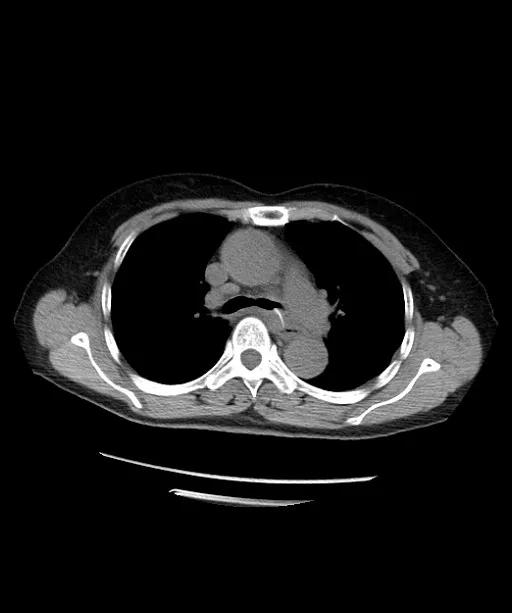

胸部CT检查发现,鱼刺已经穿透了食管壁!病情危重,老太太立即被送往急诊抢救室。

CT横断位

急诊科医生仔细查看CT,发现鱼刺处于食管第二狭窄下端,并已经穿透食管壁、纵隔、穿入左主支气管内!

对照外院CT,鱼刺有移动趋势。